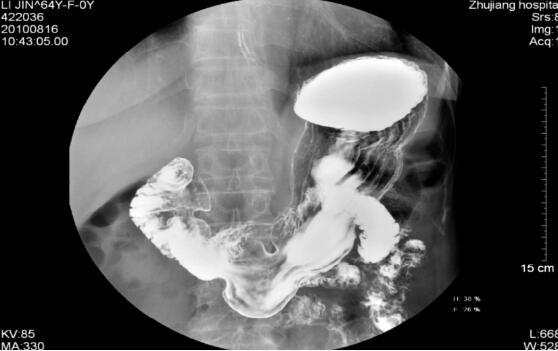

二,上消化道钡餐

消化道钡餐造影,是指口服硫酸钡造影剂后,在x线照射下显示消化道有无病变的一种检查方法,可对整个消化道,尤其是上消化道进行清晰显像的放射学检查。严重心肺疾病及危重病人,以及食管,胃肠道穿孔或食管气管瘘食管纵膈瘘,严重的吞咽困难,消化道出血及肠梗阻为检查禁忌。因为硫酸钡不溶于水,不被胃黏膜吸收,所以,对人基本无毒,检查完毕后需大量饮水,尽快排出钡餐。为避免影响诊断,3日内不宜做CT检查。